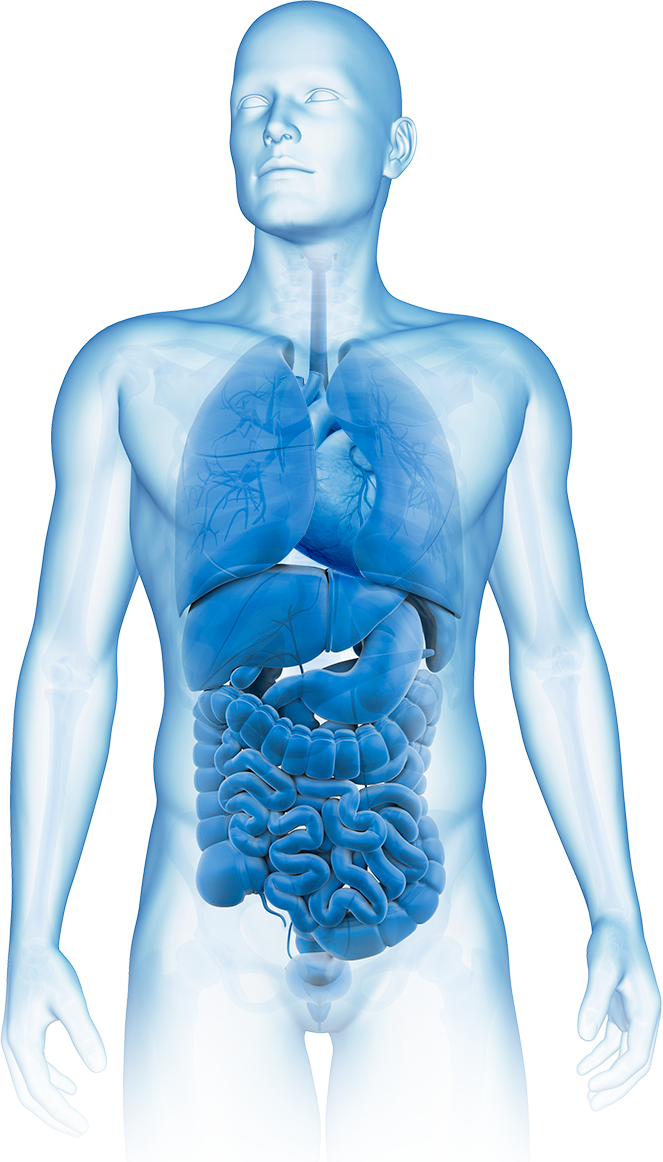

신경과 · 내과 진료를 중심으로 수액 치료와 각종 검사를

시행하고 있습니다.

신경과 · 내과 진료를 중심으로 수액 치료와 각종 검사를

시행하고 있습니다.

고혈압부터 당뇨, 소화기·호흡기 질환까지

일상 속 만성질환을 폭넓게 진료합니다.

· 알레르기성비염 · 천식/폐렴/만성폐쇄성폐질환/폐암 · 결핵 · 아토피 피부염

· 고혈압 · 협심증 · 심근경색증 · 심부전 · 부정맥 · 뇌졸증 · 동맥경화증

· 간염/지방간/간병변증/간암 · 담석증/담낭염 · 췌장염/췌장암

· 비만 · 고지혈증

· 위염/위궤양/위식도역류질환 · 과민성 대장 증후군 · 위암/대장암

· 갑상선기능저하증/갑상선항진증 · 갑상선염/갑상선결절/갑상선암 · 당뇨병